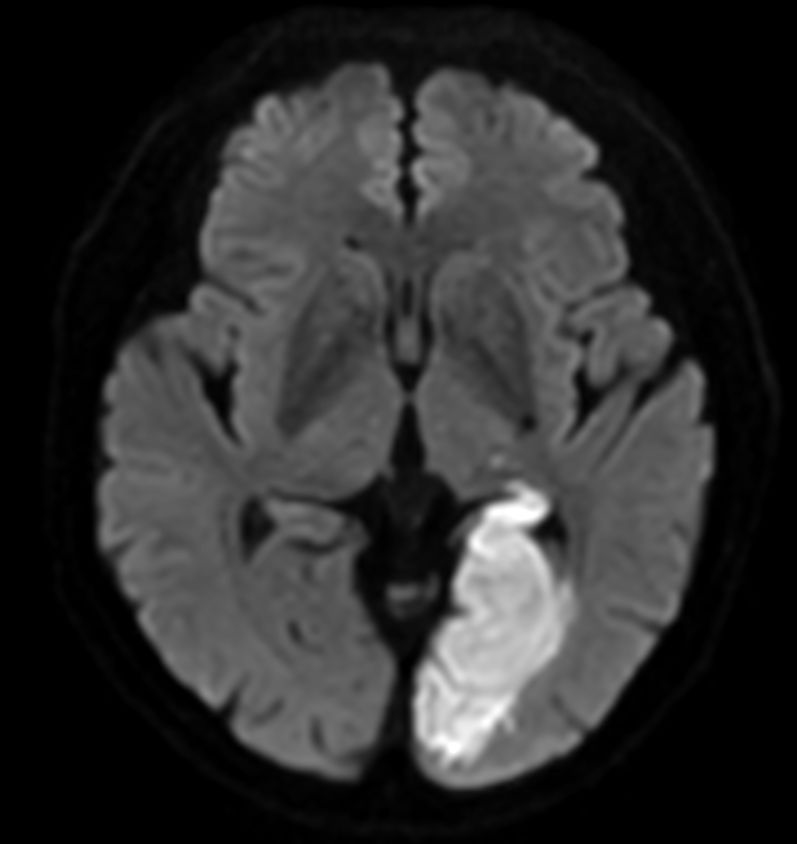

Diffusion - b1000

-

Diffusion - b1000 (ADC)